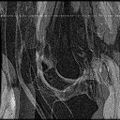

Below is the dataset of Knee MR image we used

Scatter Plot of the above two images

Segmentation Output we obtained :